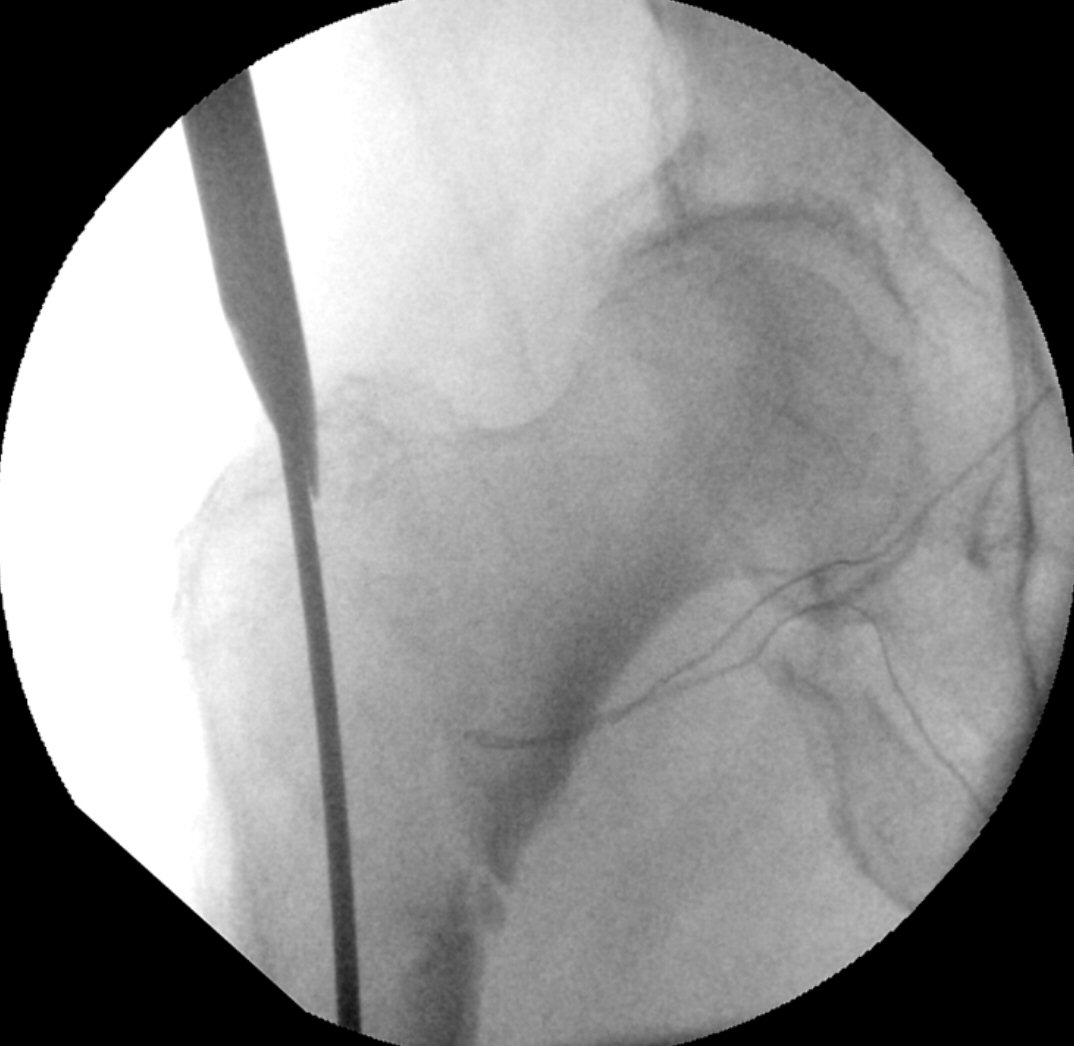

AWL med guidewire

- Kontrollera i genomlysning att guidewirern ligger inne i benet, även distalt.